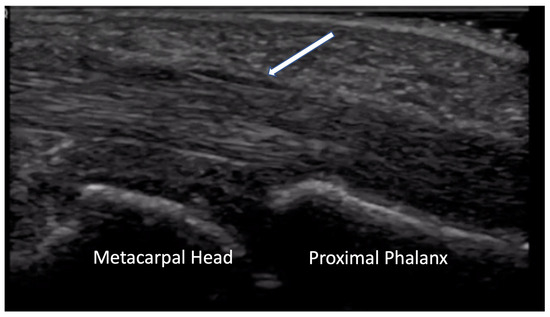

2.1.1. Non-Inflammatory Arthralgias

2.1.2. Inflammatory Arthritis